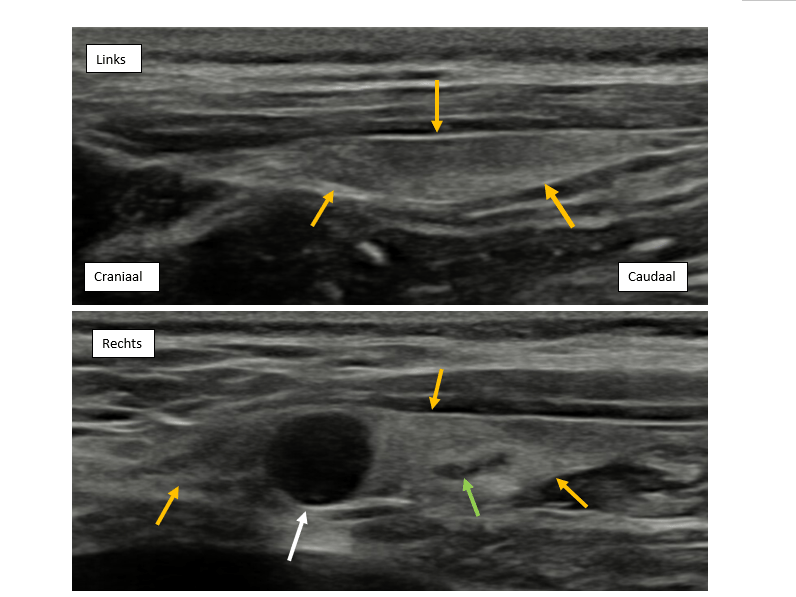

Bij Bentley was er in de craniale pool van de rechter schildklier een gering heterogene en echoarme nodule van ca. 6,6 mm zichtbaar, passend bij een vergrote bijschildklier. Caudaal in de rechter schildklier en in de linker schildklier waren er nog 2 of 3 kleine echoarme nodules zichtbaar van ca. 1-2 mm.

Fig 2. Sagittaal echografisch beeld van de beide schildklieren (gele pijlen). De rechter schildklier toont in de craniale pool een grote echoarme nodule (witte pijl; ca. 6,6 mm), passend bij een vergrote bijschildklier. Caudaal in de schildklier is een kleinere echoā-āarmere structuur zichtbaar, waarschijnlijk een normale bijschildklier.